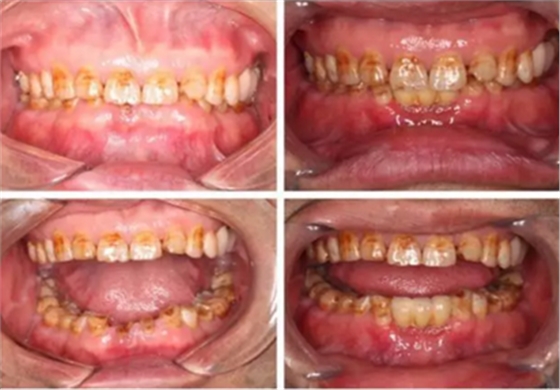

治療前后照片顯示患者上下臨床牙冠比例協(xié)調(diào),患者對(duì)臨時(shí)修復(fù)體效果十分滿意。當(dāng)然有待后期愈合及長(zhǎng)期的臨床隨訪,以觀察遠(yuǎn)期臨床效果。將水激光應(yīng)用臨床冠延長(zhǎng),有利于精準(zhǔn)去除骨量,利于術(shù)后愈合。而MINI型一段式種植體滿足骨寬度不足,及臨時(shí)修復(fù)打下堅(jiān)實(shí)基礎(chǔ)。

下圖是術(shù)后照片 治療過程 術(shù)前測(cè)量上下牙長(zhǎng)度比例,確定水激光冠延長(zhǎng)深度約3mm,拔除31、41,在術(shù)區(qū)減低牙槽嵴高度,32、42位點(diǎn)種植MINI型一段式種植體,使用臨時(shí)愈合帽行暫時(shí)性修復(fù)。